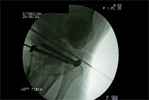

Op

Lateral Tibial Plateau Elevated and Wire inserted

2nd Wire inserted into elevated lateral tibial plateau